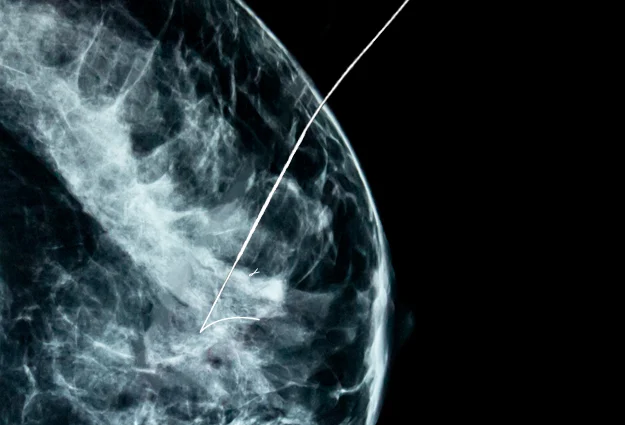

The most prevalent malignancy, breast cancer, is becoming more and more prevalent, and its numerous diagnosis options, including early detection and screening, are promoting the expansion of the breast lesion localization market. The early detection, screening, and treatment of breast cancer based on that diagnosis have significantly increased the breast lesion localization market. Breast cancer is the second-leading cause of cancer-related deaths among women globally.

The Breast Lesion Localization Market is anticipated to grow at a 4.1% CAGR through 2032, from a market size of US$ 256 million in 2022 to US$ 382 million by 2032, according to the FMI report.

- Breast Biopsy segment is the largest segment by the usage type and will hold the biggest portion of the market in the forecast period, thriving at CAGR of 3.5% through 2032. The growth of segments is attributed to easy removal and short time span and lower post-surgery impacts than the lumpectomy.

- Hologic Inc has introduced LOCalizer, the wire-free breast lesion system that is designed to mark and guide non-palpable breast lesions using a miniature. This innovative technology pushes the market and increases the demand for breast lesion localization processes.